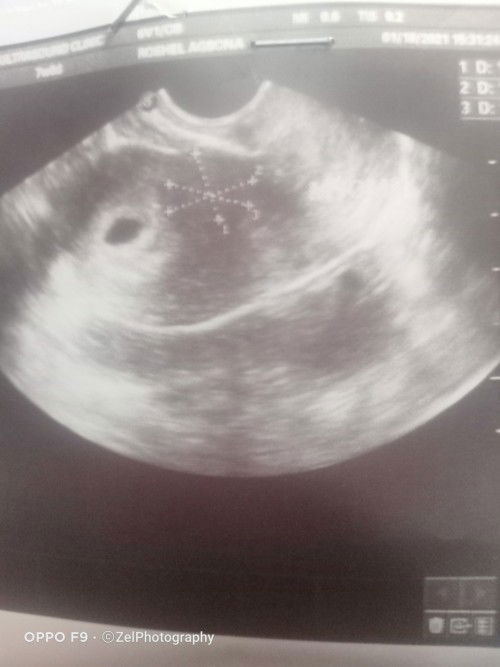

I have mayoma about 1 inch and I'm 6weeks pregnant, can you suggest what to do? Having bed rest now.

I was checked by my OB already and adviced for bed rest. #1stimemom #pregnancy #advicepls